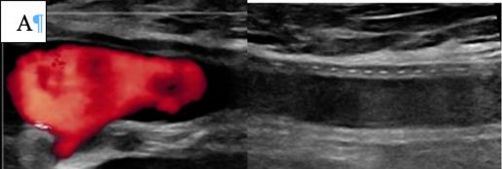

После чрескожной пункции общей бедренной артерии (ОБА) достаточно часто возникают паховые гематомы. Для предотвращения данного осложнения следует избегать сквозной пункции общей бедренной артерии.

• Рекомендуется проводить пункцию под ультразвуковым контролем с целью точного прокола передней стенки артерии и минимизации риска повреждения задней стенки [185, 186].

Комментарий: Анализ пяти РКИ показал, что пункция артерии под УЗ-контролем снижает частоту осложнений по сравнению с пункцией по анатомическим ориентирам [180]. Использование УЗИ уменьшало число попыток пункции (ОШ 0,24), риск прокола вены (ОШ 0,18) и кровотечений (ОШ 0,41). Сравнительных данных об эффективности антеградного и ретроградного доступа при тромболизисе нет. Антеградный доступ через ОБА упрощает реканализацию тромбозов дистальных артерий, а через артерии верхней конечности – прохождение через тромбированную бифуркацию аорты. Ретроградный контралатеральный доступ через ОБА наиболее распространён, обеспечивает стабильное положение катетера и снижает риск смещения и кровотечения [181]. Этот доступ также позволяет избежать необходимости сдавления ОБА ишемизированной нижней конечности при гемостазе, после удаления набора для чрескожного сосудистого доступа (интродьюсер) из места пункции.

• При выполнении эндоваскулярного вмешательства пациентам с острой ишемией конечностей рекомендуется проводить пункцию артерии доступа под ультразвуковым контролем [181].